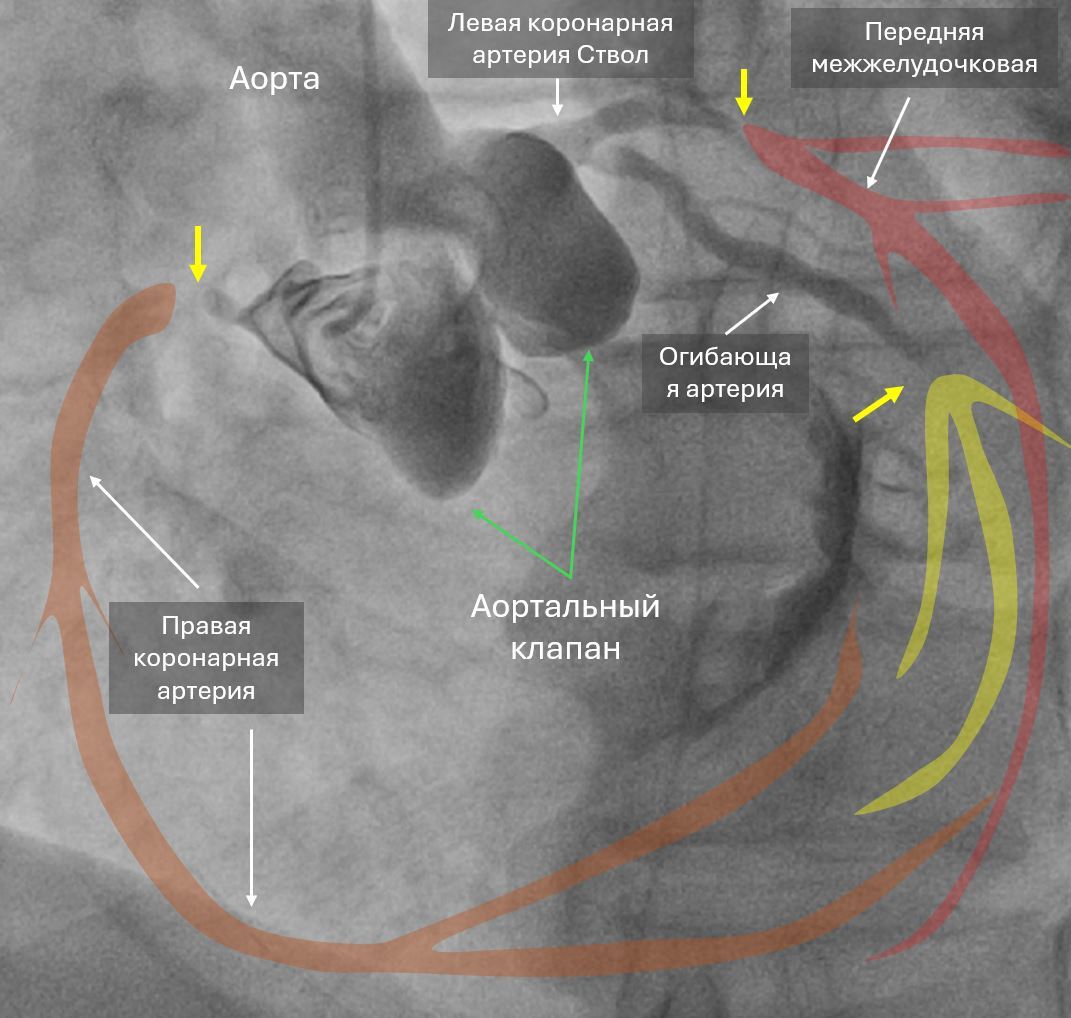

8 утра, мужчина 66 лет, боли в груди с 3 ночи, скорая, в машине 7 раз фибрилляция желудочков, ЭДС, перевод на ИВЛ, с приемника на стол на коронарографию, при перекладывании опять остановка, наружный массаж, адреналин, ЭДС, пункция по ориентирам, введен катетер и такая картина - закрыты все три артерии, сердце стоит, на ЭКГ электрическая активность сохранялась еще минут 15 (электромеханическая диссоциация). На вскрытии циркулярный инфаркт, шоковые органы.